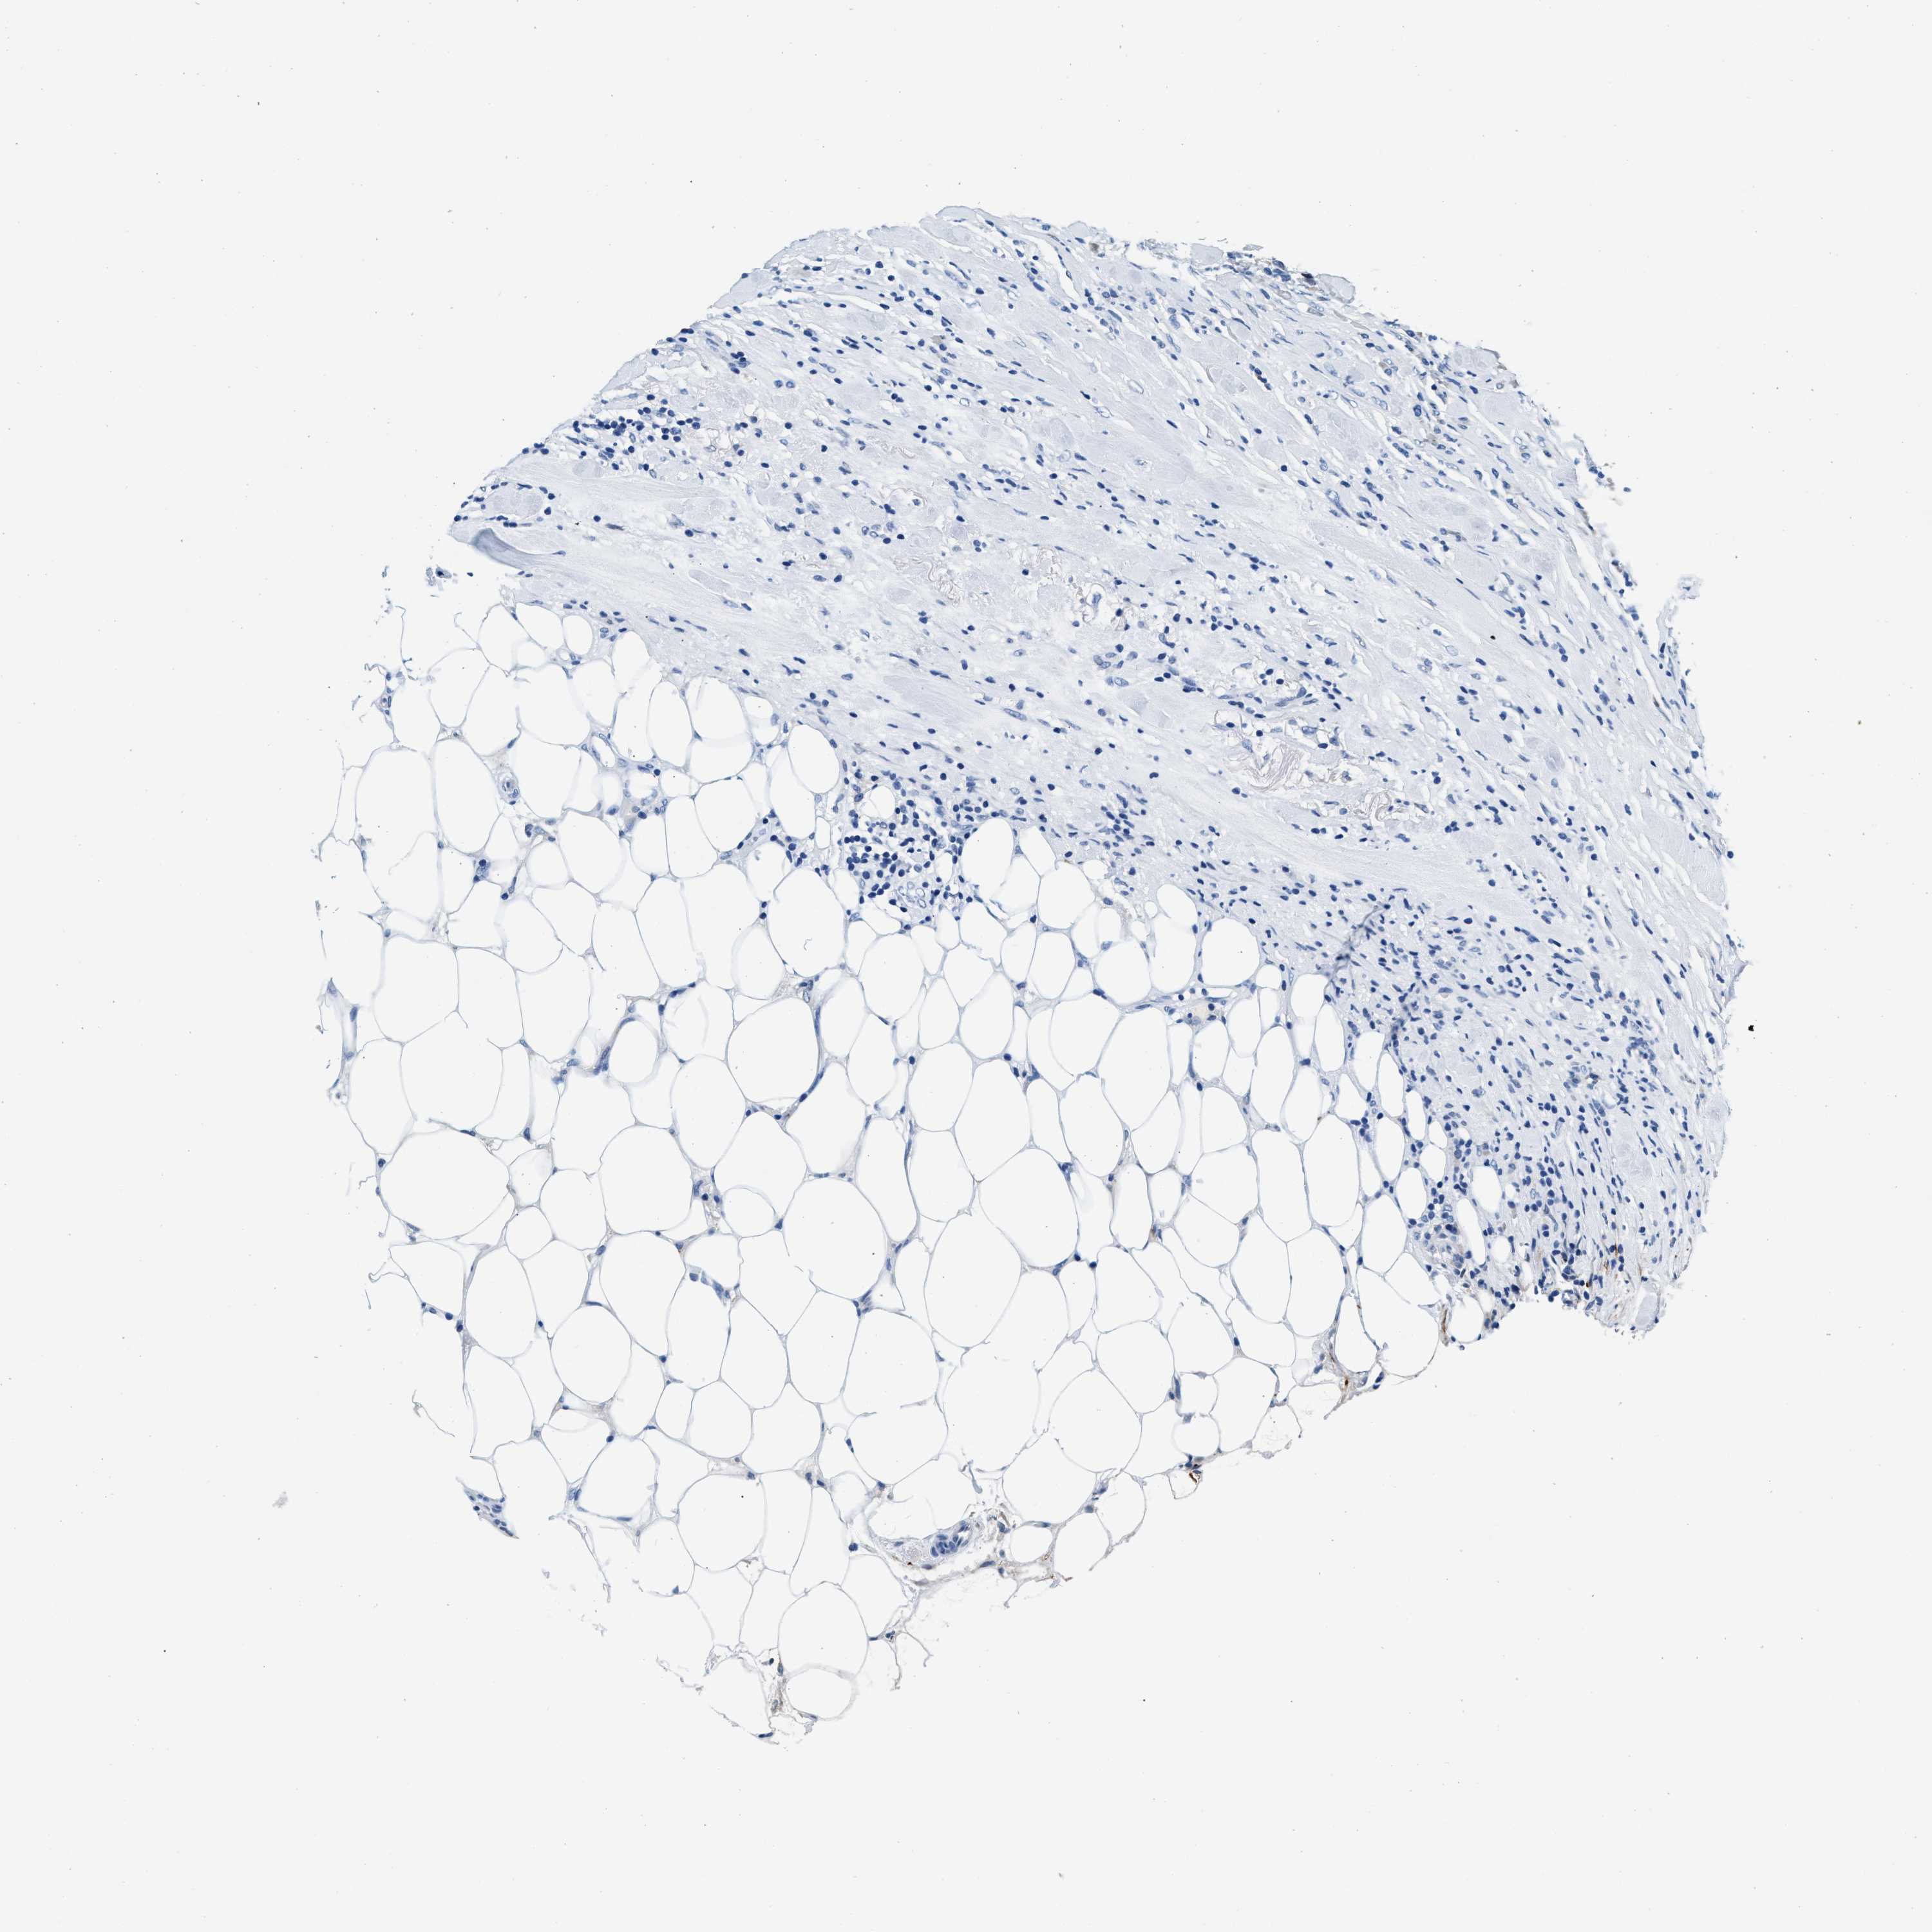

CANCER BREAST CANCER Show tissue menu

BRCA TCGA BRCA VALIDATION PROTEIN EXPRESSION